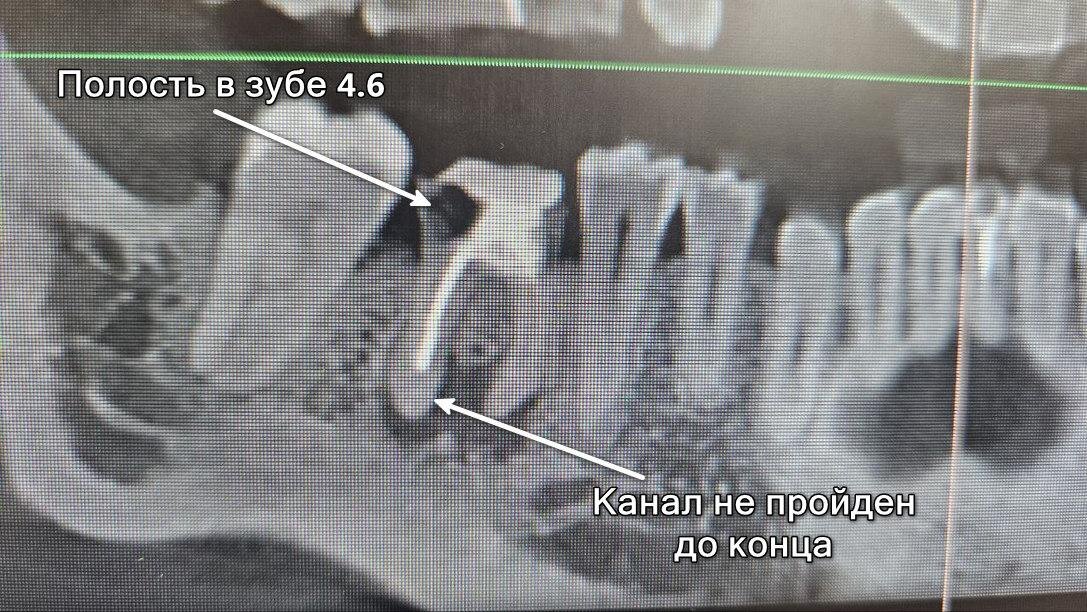

Ольга мечтала восстановить зуб 4.6 пломбой или коронкой. Рентгенологическое исследование показало, что зуб уже был пролечен ранее, но не долечен. Канал запломбирован не до конца. Удаление пломбировочного материала и попытка полностью пройти канал — рискованный план, корень зуба скорее всего треснет.